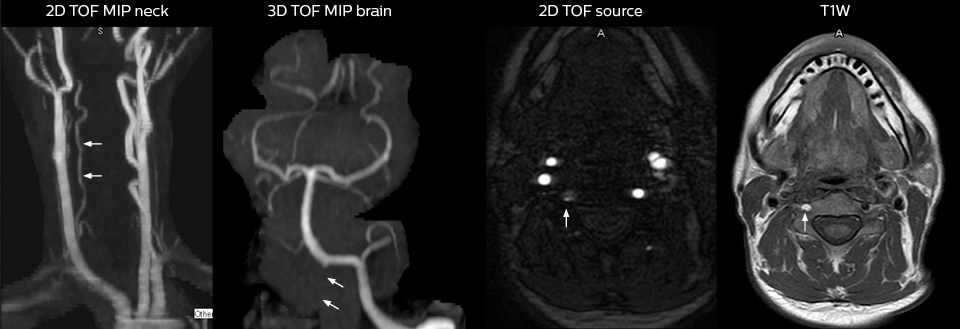

Future plans: expansion to stroke and TIA patients

At St. Joseph’s Hospital and Medical Center, the dedicated MRI system in the ED has been shown to efficiently provide high quality MR images that assist physicians in making informed decisions on patient diagnoses and take a more definitive decision on follow-up. The decision to have a dedicated ED MRI has resulted in rapid patient turnaround, efficient patient management, and substantial reductions in radiation dose.

For Dr. Karis, the next goals for the neuro ED include converting the exams for acute stroke and TIA patients from CT to MRI, offering an alternative management option for these patients. Also, collaboration between other departments is currently underway, encouraging the performance of targeted exams with the ED MRI. These improvements in workflow and faster turnaround times may result in further reductions in scanning time.